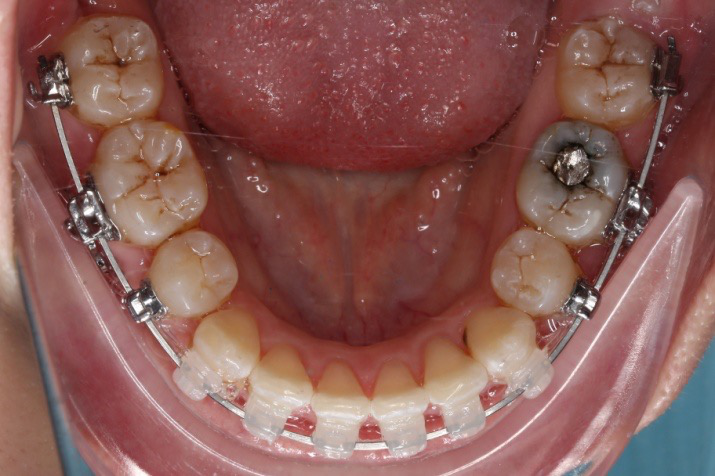

2017.04.28

2017.04.28  上0.016*25ss 13、23近远中约5度 v形曲,下0.017*25ss

2017.05.26  磨牙近中倾斜,下颌36、46加power arm

2017.07.25

2017.07.25  上前牙加颈部弹力线

下颌磨牙通过powerarm直立效果明显,下颌整平效果明显